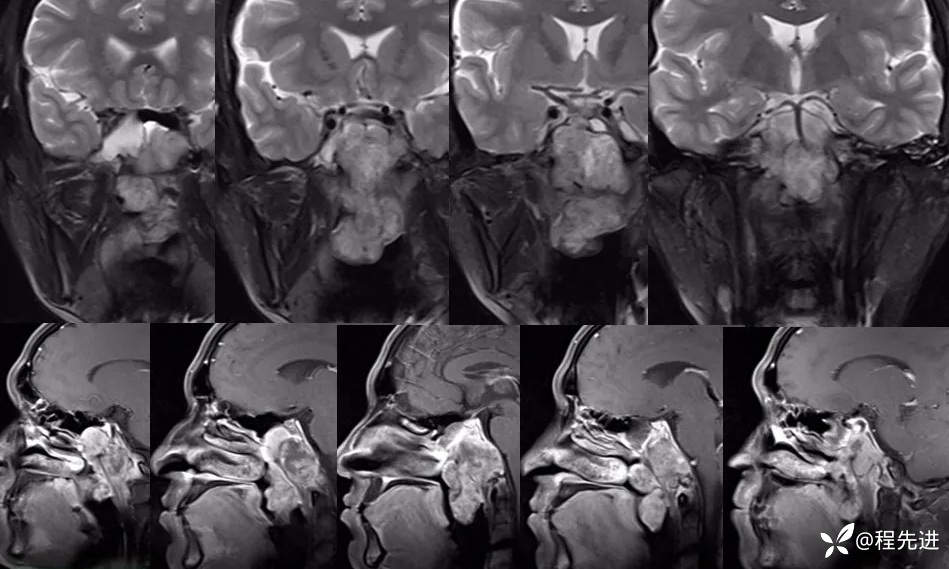

冠状位T2、矢状位T1增强: